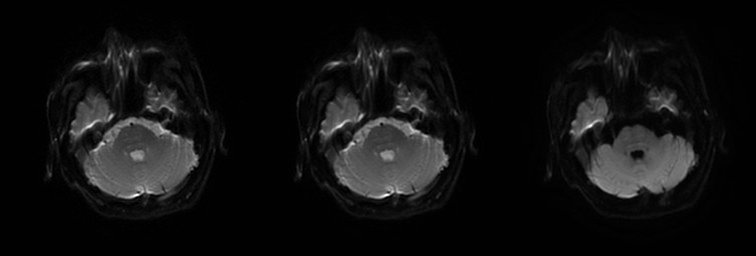

(2)CPM,病灶多位于桥脑基底部而桥脑腹侧不受累,病灶形状多种多样,可为条片状(位于中脑基底部中线,如本例)、斑片状、圆形或卵圆状、「三叉戟」或「猪鼻」样,T1WI 呈低信号,T2WI 及 FLAIR 呈高信号,病灶边界清晰,部分患者出现 DWI 高信号,有利于疾病的早期发现,出现强化提示血脑屏障破坏。

(3)EPM,病灶多对称位于基底核团或丘脑,少数病例可累及皮层,信号表现与 CPM 相似,但病灶形态不相同

(4)CPM+EPM:(2) (3),MRI 与临床表现不密切相关,一般都会滞后几个星期。